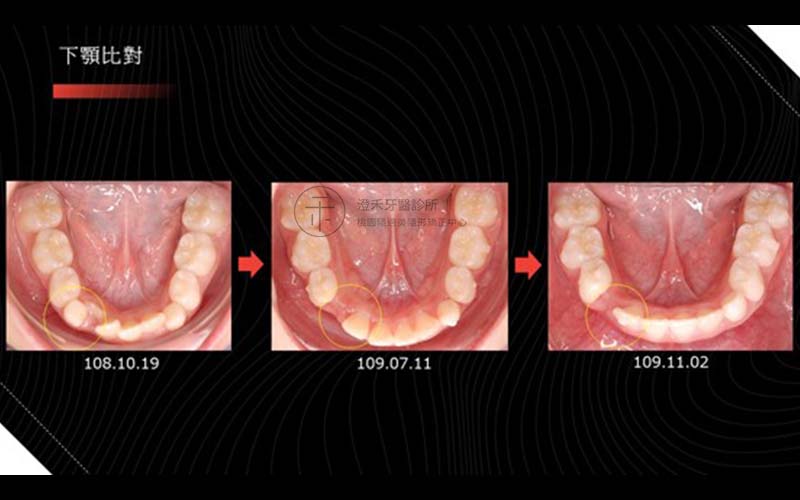

案例六

年齡:8歲

初期配戴MRC牙托,第二階段配戴隱適美矯正器,改善深咬、小下巴,以達到擴弓成果。

矯正療程:10M